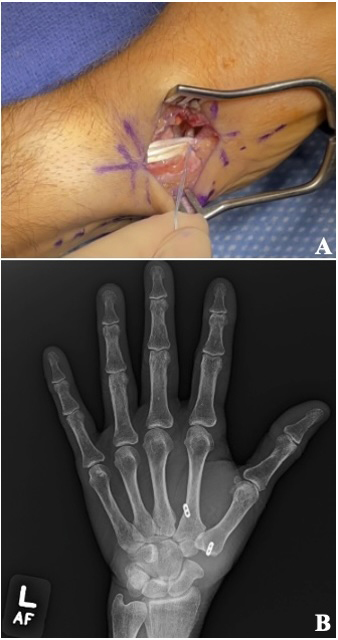

Trapeziometacarpal arthrodesis (TMA) of the thumb is typically performed by fusing the metacarpal in approximately 45° of radial and palmar abduction and slight pronation to allow an opposable thumb to all four digits [Figure 1].12 Rigid fixation is performed using K-wires, tension band fixation, staples, headless compression screws, and/or plates and screws in isolation or combination.12–14 The CMC1 joint is immobilized until clinical and radiographic union.12 This technique is typically considered for advanced CMC1 osteoarthritis in active, young, high-demand individuals and manual laborers who require a stable joint.12,15 Relative contraindications include STT or pantrapezial arthritis, an unstable metacarpophalangeal joint, or an inability to tolerate a fixed trapeziometacarpal joint.12